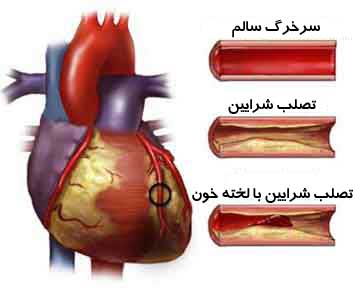

علل سکته قلبی

سکته قلبی معمولا وقتی اتفاق میافتد كه لخته خونی در مسیر جریان خون عروق كرونری ـ كه تغذیهكننده عضله قلبی…

مهمترین علت سکته قلبی

میزان مرگ و میر ناشی از بیماریهای قلبی 25 % و مرگ و میر ناشی از سکته مغزی در حدود…

علت بروز سکته قلبی

سکته به معنی حادثه است. سکته قلبی به معنی حمله قلبی و علتش بسته شدن و انسداد رگهای خون دهنده قلب…